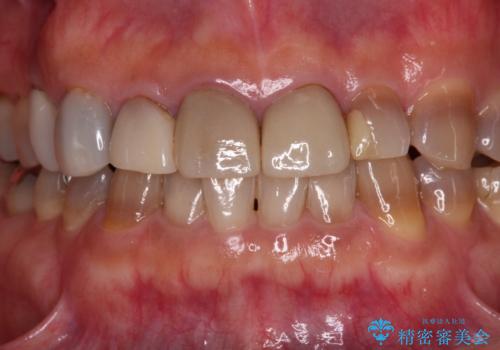

- 前歯のテトラサイクリンによる変色歯と、レジン充填の色の違いを気にして来院された患者様です。

患者様の希望により、前歯6歯をオールセラミッククラウンにて補綴することとしました。

長年前歯の色の違いに悩んでいらっしゃったようですが、仮歯に変えた時点で統一感のある白さとなり喜んで頂きました。

わずか1ヶ月の間にとても自然な仕上がりのセラミッククラウンが装着され、患者様には大変満足していただきました。